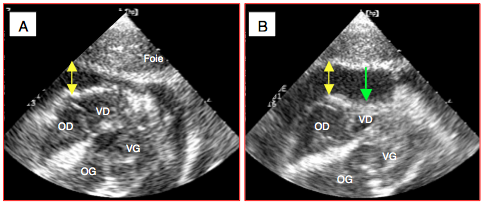

Le champ d'application de cette échocardiographie dirigée est restreint à des situations où l'écho peut répondre de manière binaire (oui/non, présent/absent) à des questions soulevées par la prise en charge immédiate du patient en choc hémodynamique [10,12,13,20,21].

- Défaillance ventriculaire droite (dimension télédiastolique, fonction systolique, position du septum interventriculaire);

- Epanchement péricardique, tamponnade;